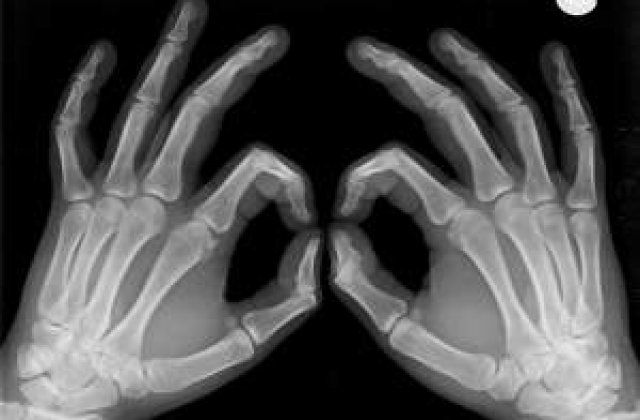

Metoda savantilor a detectat diminuarea masei osoase dupa doar o saptamana de odihna la pat, mult mai repede decat tehnicile medicale conventionale de radiografiere.